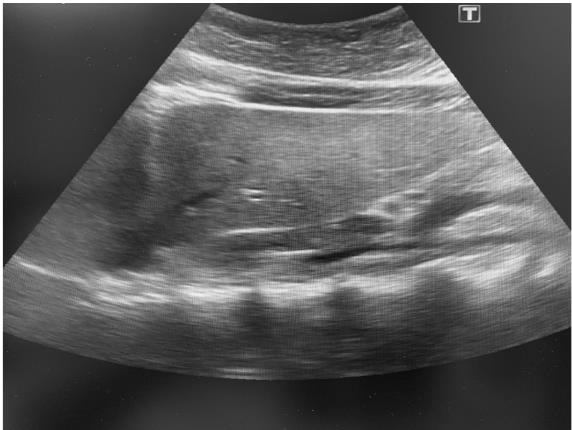

Иллюстрация к книге — О чем молчит печень. Как уловить сигналы самого крупного внутреннего органа, который предпочитает оставаться в тени [i_096.jpg]

Рис. 62. Внешний вид печени на УЗИ